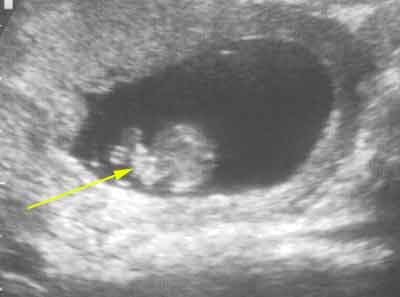

Coupe transversale